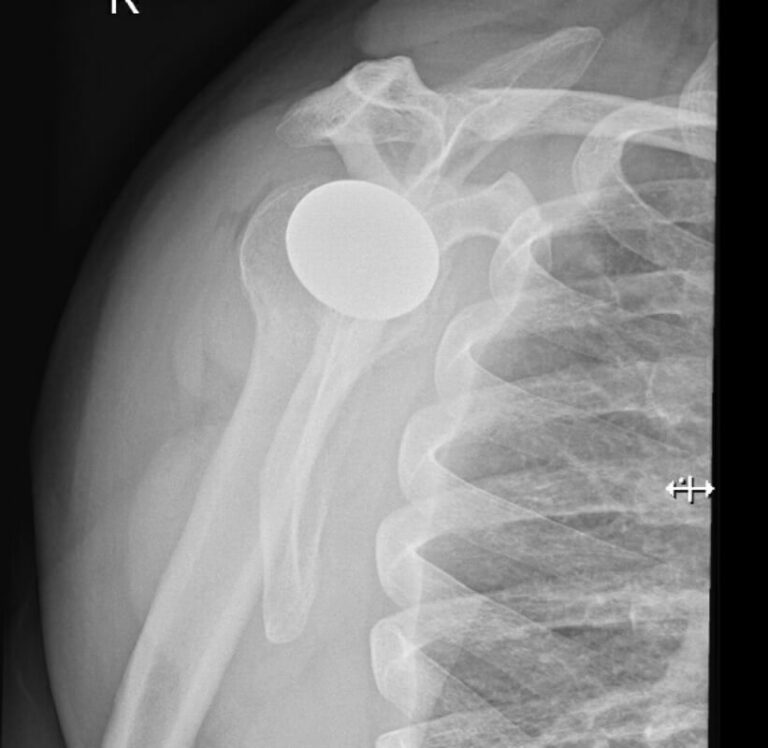

Arthrosurface, HemiCap Large